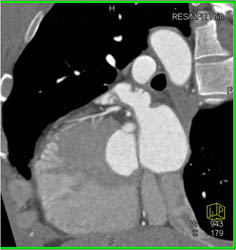

Plaque in LAD